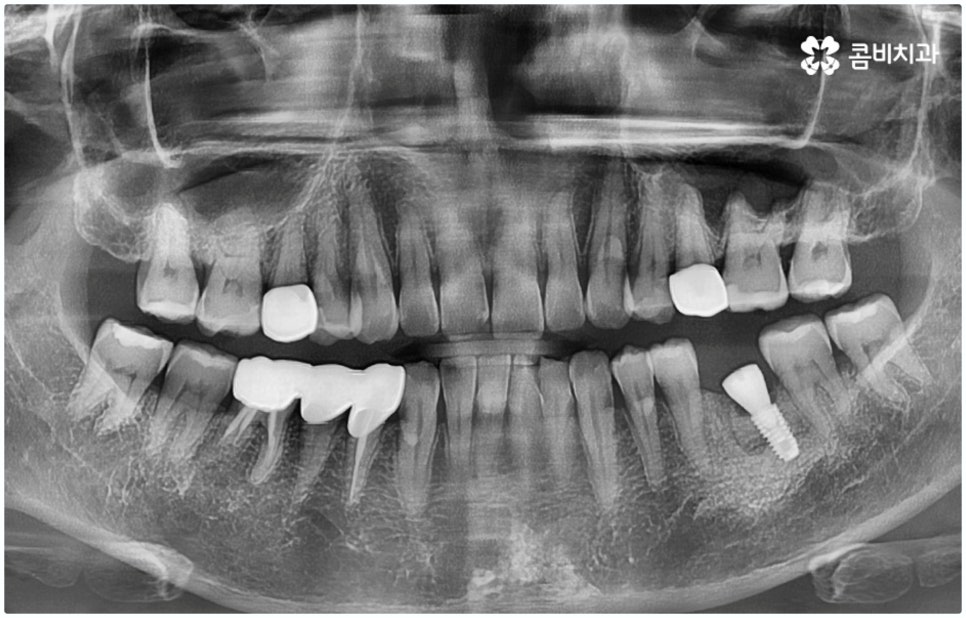

통상적으로 임플란트 시술 과정이 3~6개월 정도 소요되는데 반해 원데이임플란트 란 말 그대로 발치 후 식립 및 임시보철물까지 당일에 장착하는 방법이기 때문에 많은 분들이 선호하시고 있는데요. 하지만 누구나 원데이임플란트 치료가 가능한 것은 아니므로 검진부터 받아보셔야 할 거예요

임플란트 시술은 사람의 잇몸뼈와 잘 붙고 인체에 무해한 인공치근(픽스처)을 식립한 후 중간 연결 부분인 지대주와 치아 머리 부분인 크라운을 차례대로 연결하여 기능상 심미상으로 자연 치아를 대체해 주는 인공 치아 식립 방법으로 보통 픽스처를 심을 때 잇몸뼈와 제대로 유착되는 시간이 필요하기 때문에 중간에 일정 시간 회복기를 두고 진행하게 되어 있어요.

이때 환자분들의 상황에 따라 잇몸뼈가 충분하지 않다면 먼저 뼈이식을 통해 이를 단단하게 보충해 주기도 하고, 치주 질환의 치료가 필요하거나 상악동과의 거리가 너무 짧아 거상술이 필요한 경우 이를 선행하기도 하기 때문에 전체 기간은 개개인에 따라 달라질 수 있으며 특히 구강 상태나 연령에 따라 충분한 회복 및 적응 시간을 두지 않으면 식립 성공률이나 장기적인 지속성에 좋지 않은 영향을 줄 수 있으니 주의할 필요가 있습니다.

그렇기 때문에 무조건 보다 빠르고 간편하다고 해서 원데이임플란트 방법을 고집하기 보다는 개인 상태에 따라 필요한 과정을 세심하게 맞춤 진행할 수 있도록 경험이 풍부하고 노하우가 뛰어난 의료진에게 치료 받는 것이 중요한 거예요. 즉 3D CT 등 정밀 검진 장비를 이용하여 환자분들의 치아 및 잇몸 상태, 치아 배열과 교합상태, 주변 치아와의 관계 및 조화까지 꼼꼼하게 파악할 뿐 아니라 턱뼈, 혈관, 신경 등 구강 전체를 함께 분석한 후 체계적인 시술 계획을 세워 각자에 맞는 방법으로 무리하지 않게 수술을 진행할 수 있는 숙련된 의료진과 함께 하는 것이 무엇보다 중요하다고 할 수 있습니다.